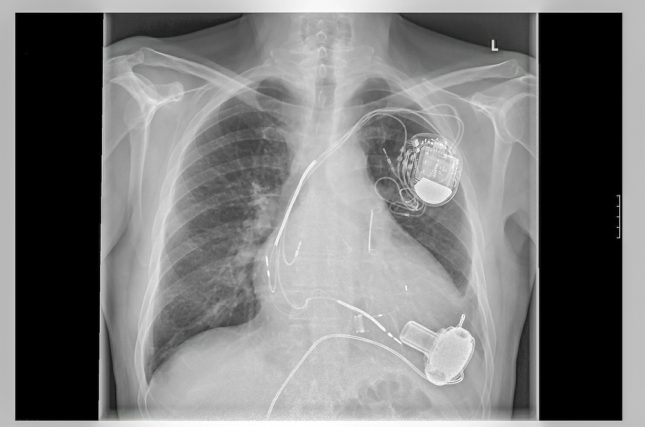

טיפול CRTי– cardiac resynchronization therapy הודגם כבעל השפעה מיטיבה באנשים עם אי ספיקת לב עמידה לטיפול תרופתי. למרות, שהטיפול יעיל במגוון אטיולוגיות לקרדיומיופתיה שאינה אסכמית תפקידה בשיפור עיצוב מחדש (remodeling) ושרידות באנשים עם סרקואידוזיס לבבית אינו מוגדר.

החוקרים ביצעו סקירה רטרוספקטיבית של כלל המטופלים במוסד רפואי בודד עם סרקואידוזיס לבבית אשר עברו השתלת CRT בין השנים 2007-2017. התוצאים באוכלוסייה זו השוו עם התוצאים של עוקבה של מטופלים עם קרדיומיופתיה שאינה אסכמית בשל אטיולוגיה אחרת מסרקואידוזיס.

במהלך תקופת המעקב 19 מטופלים עם סרקואידוזיס לבבית עברו השתלת CRT. הקבוצה הזו הושוותה עם 311 מטופלים קרדיומיופתיה שאינה אסכמית בשל אטיולוגיה אחרת מסרקואידוזיס שעברו גם כן השתלת CRT.

החוקרים מצאו כי CRT שיפר מקטע פליטה של חדר שמאל מ-28.8% ל-35.9% (p<0.05) בסרקואידוזיס לבבית בעוד שהשיפור בקבוצה ללא סרקואידוזיס היה מ-25.0 ל-36.6% (p<0.01).יCRT שיפר באופן מובהק סטטיסטית מקטע פליטה של חדר שמאל במטופלים עם סרקואידוזיס לבבית.

החוקרים מסכמים כי אין עדות לכך שהתוצאים לאחר השתלת CRT במטופלים עם סרקואידוזיס לבבית פחות טובים מאשר מטופלים עם סיבות אחרות לקרדיומיופתיה שאינה אסכמית.